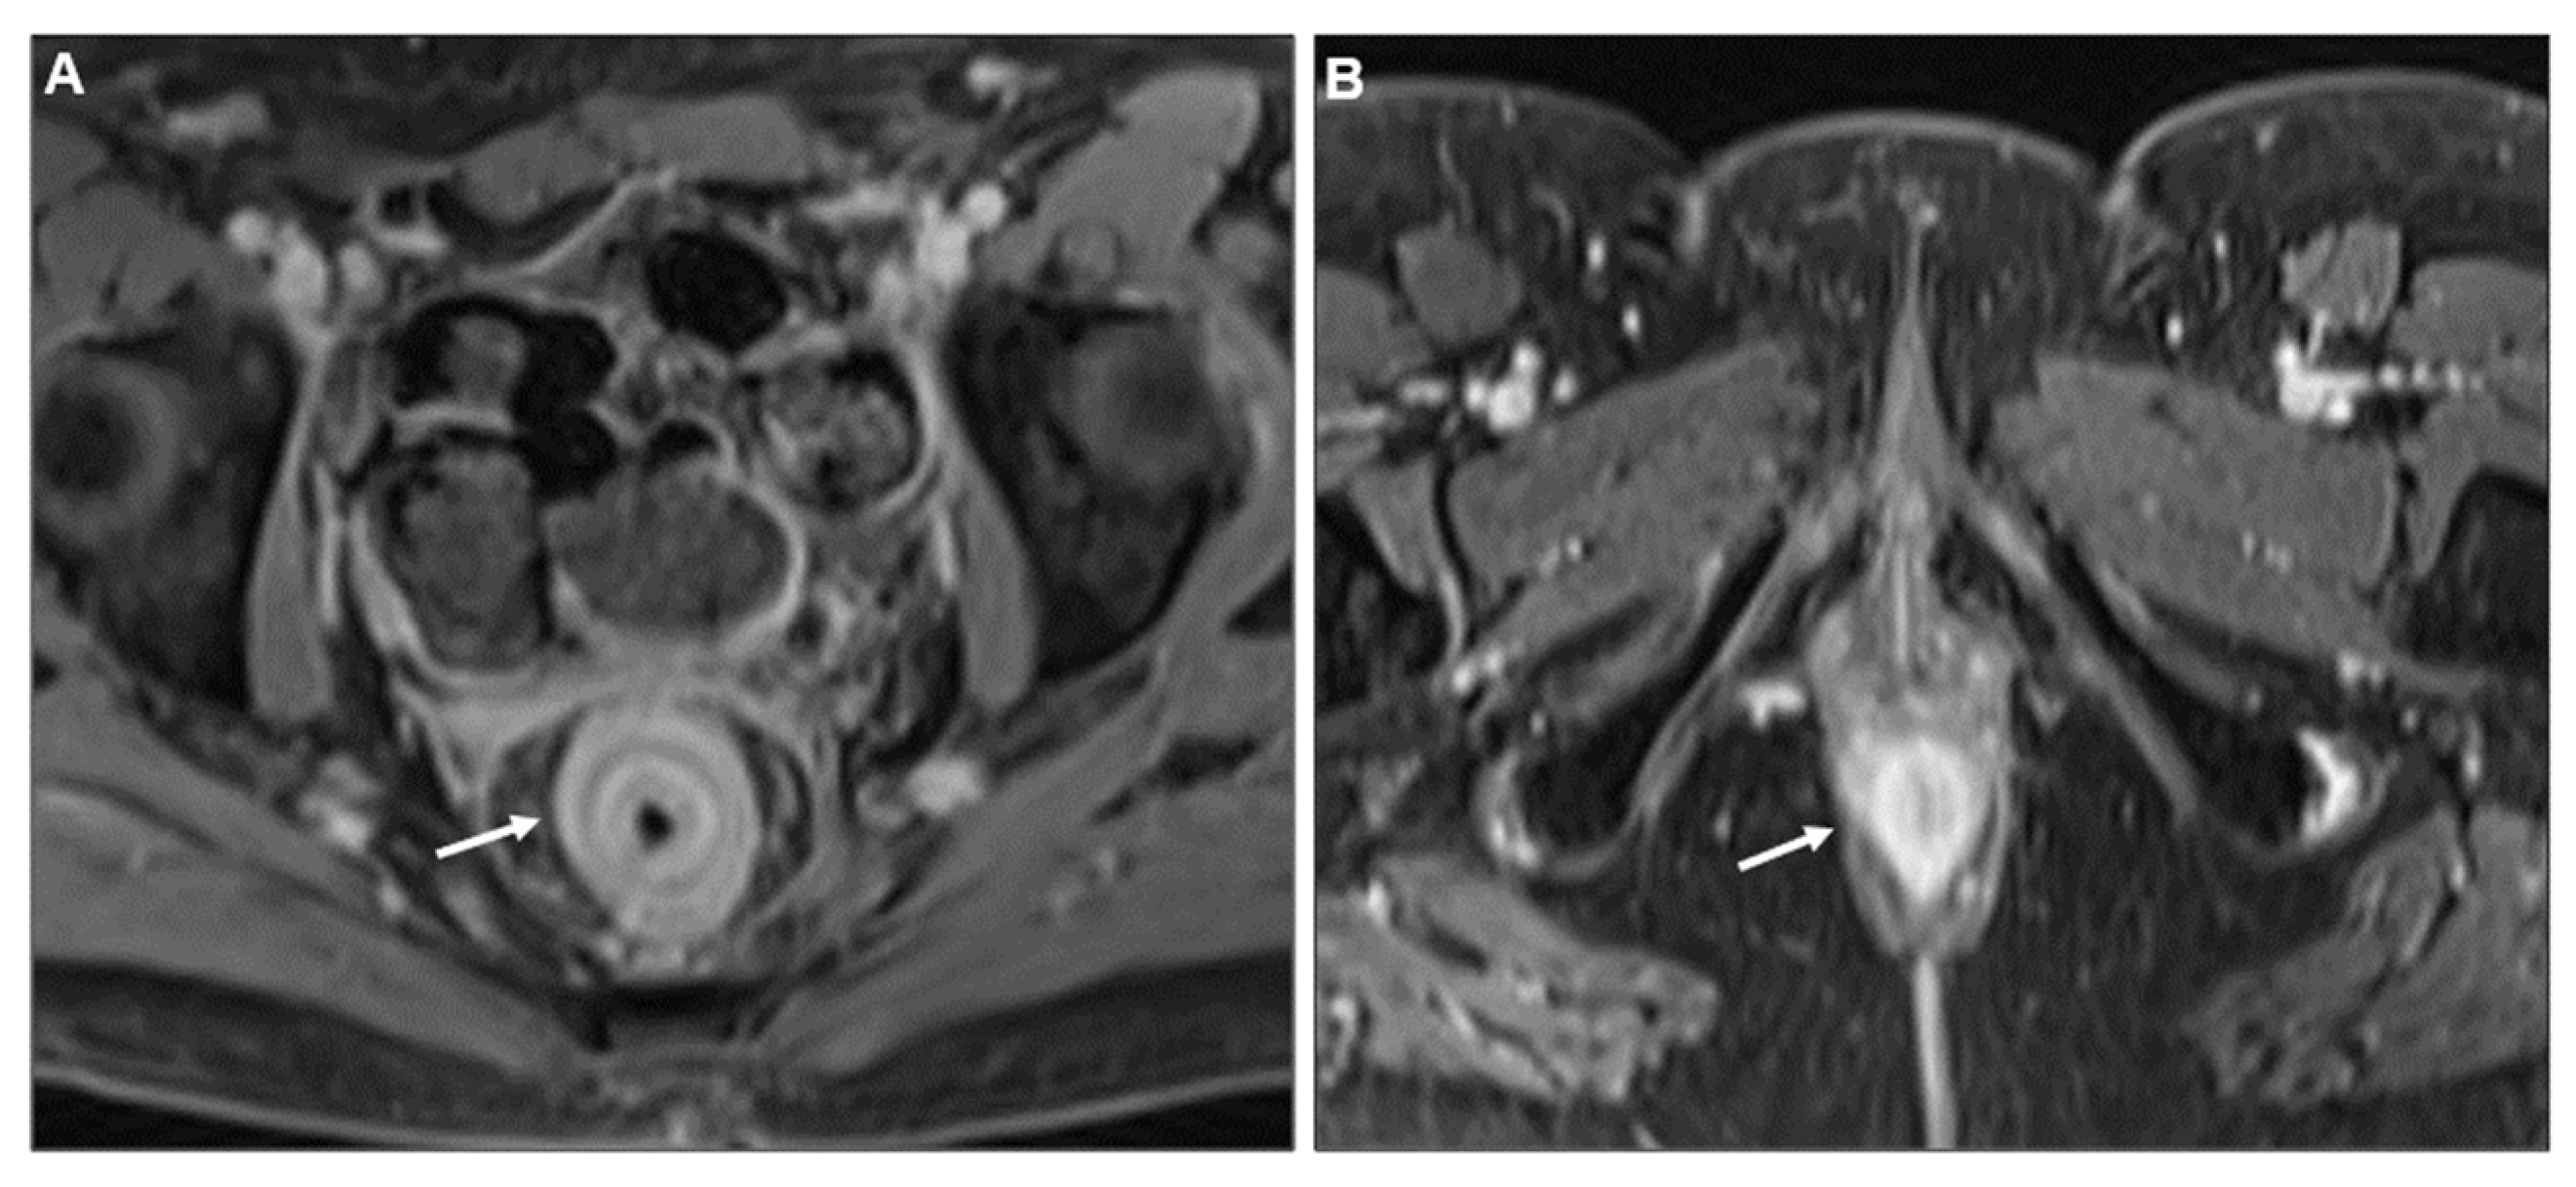

Concentric Ring Pattern

- Lau, L.C.; Wee, B.; Wang, S.; Thian, Y.L. Metastatic breast cancer to the rectum: A case report with emphasis on MRI features. Medicine 2017, 96, e6739. [Google Scholar] [CrossRef] [PubMed]

- Rudralingam, V.; Dobson, M.J.; Pitt, M.; Stewart, D.J.; Hearn, A.; Susnerwala, S. MR imaging of linitis plastica of the rectum. AJR Am. J. Roentgenol. 2003, 181, 428–430. [Google Scholar] [CrossRef] [PubMed]

- Mazza, S.; Laurenza, C.; Elvo, B.; Tanzi, G.; Ungari, M.; Soro, S.; Verga, M.C.; Drago, A.; Grassia, R. Rectal linitis plastica as the first presentation of metastatic lobular breast cancer: An endoscopic ultrasound diagnosis. Clin. J. Gastroenterol. 2022, 15, 1072–1077. [Google Scholar] [CrossRef] [PubMed]

- Mommersteeg, M.C.; Kies, D.A.; van der Laan, J.; Wonders, J. Linitis plastica of the rectum secondary to prostate carcinoma. BMJ Case Rep. 2022, 15, e248462. [Google Scholar] [CrossRef]